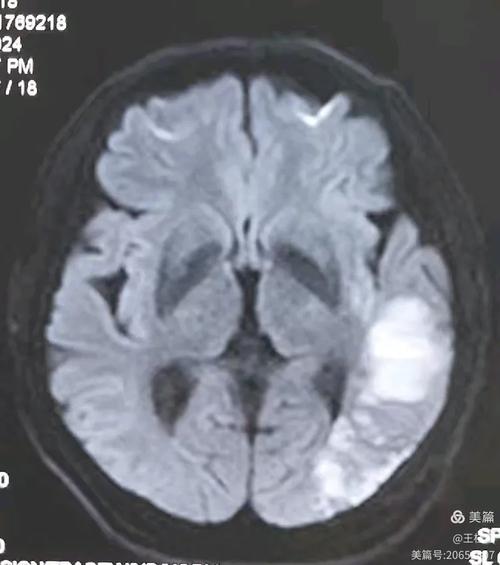

DWI序列(弥散加权成像)—— “脑梗的照妖镜”

这是诊断急性脑梗最最关键的序列。

- 图片表现:在正常的脑组织背景上,梗死的区域会显示为一个非常亮的白色高信号。

- 原理:急性梗死的脑细胞水肿,细胞膜破裂,细胞内的水分子运动受到极大限制,无法自由“弥散”,DWI序列对水分子的自由运动非常敏感,运动受限的区域信号就异常增高,呈现出亮白色。

- 临床意义:只要在DWI上看到明确的亮白斑,医生就可以高度怀疑是新鲜的脑梗死,并立即进行溶栓或取栓等治疗,这是时间窗内(通常发病后4.5-6小时内)决定治疗的关键依据。

示例图(模拟):

(图片来源网络,侵删)

- 左侧是正常的DWI图像,脑组织信号均匀。

- 右侧是急性脑梗患者的DWI图像,红色箭头所指的白色高信号区域就是急性梗死灶。